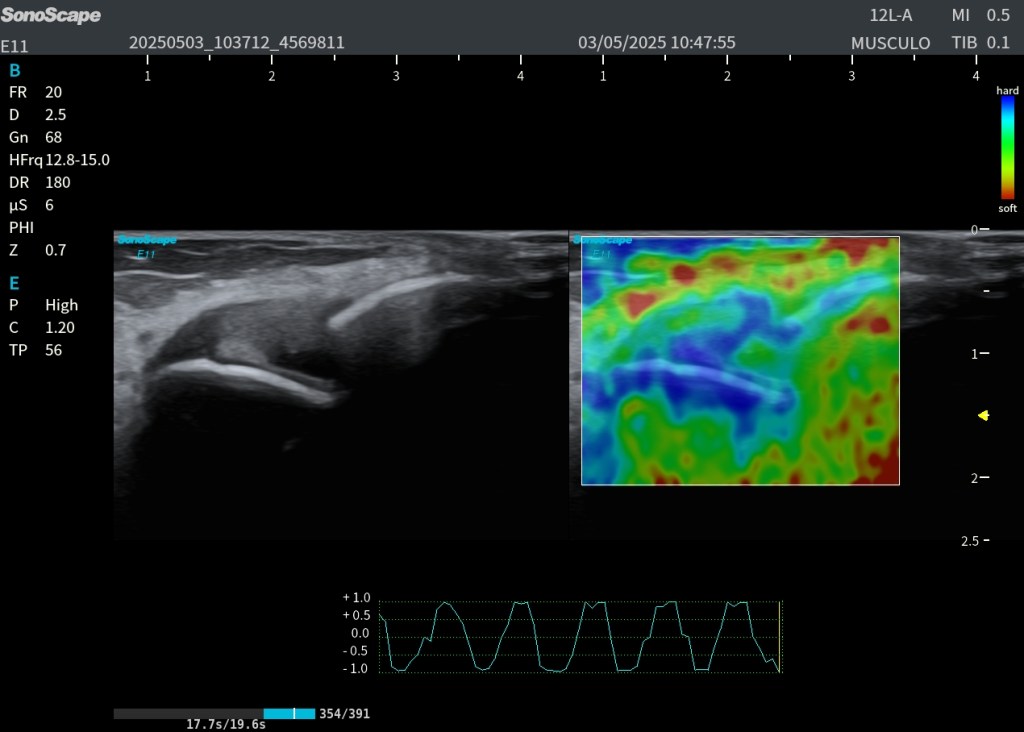

🧠 Elastografía: Rigidez Ligamentaria

En la imagen inferior derecha se ha realizado elastografía por Strain, que permite valorar la elasticidad de los tejidos:

- El ligamento se muestra en azul, indicando mayor rigidez en la zona lesionada.

- Las partes blandas y tejido graso periférico aparecen en rojo, reflejando menor rigidez y mayor elasticidad.

Este análisis complementario ayuda a estratificar la fase de la lesión y orientar la rehabilitación, ya que un ligamento más rígido puede indicar proceso cicatricial avanzado.